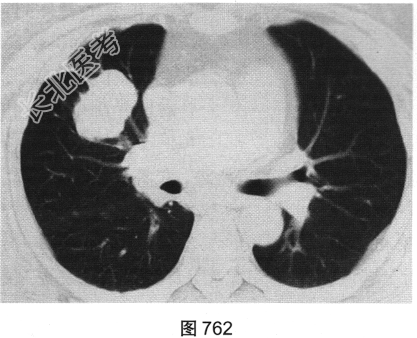

- 多项选择题2.[提示]患者行胸部CT检查,如图762、图763所示。胸部CT如图所示, 超声心动图显示心功能降低,冠状动脉CTA除显示原支架内轻度狭窄外, 未见其他异常。为明确病变性质,下一步应进行哪些检查( )